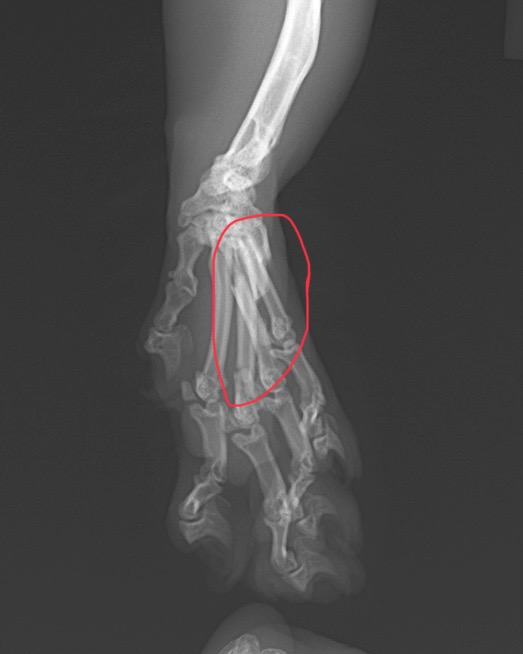

中手骨の骨折が認められました。(第3-5指)

今回はピンニングによる整復を行いました。

現在、経過は良好です。